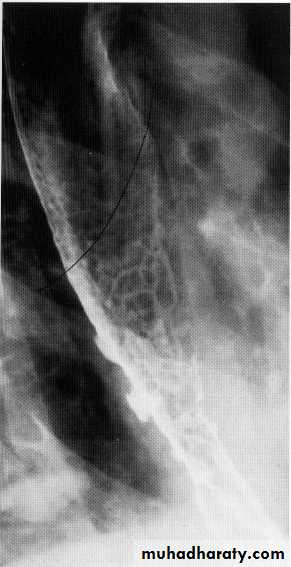

Tertiary contractions

Advanced esophageal Ca